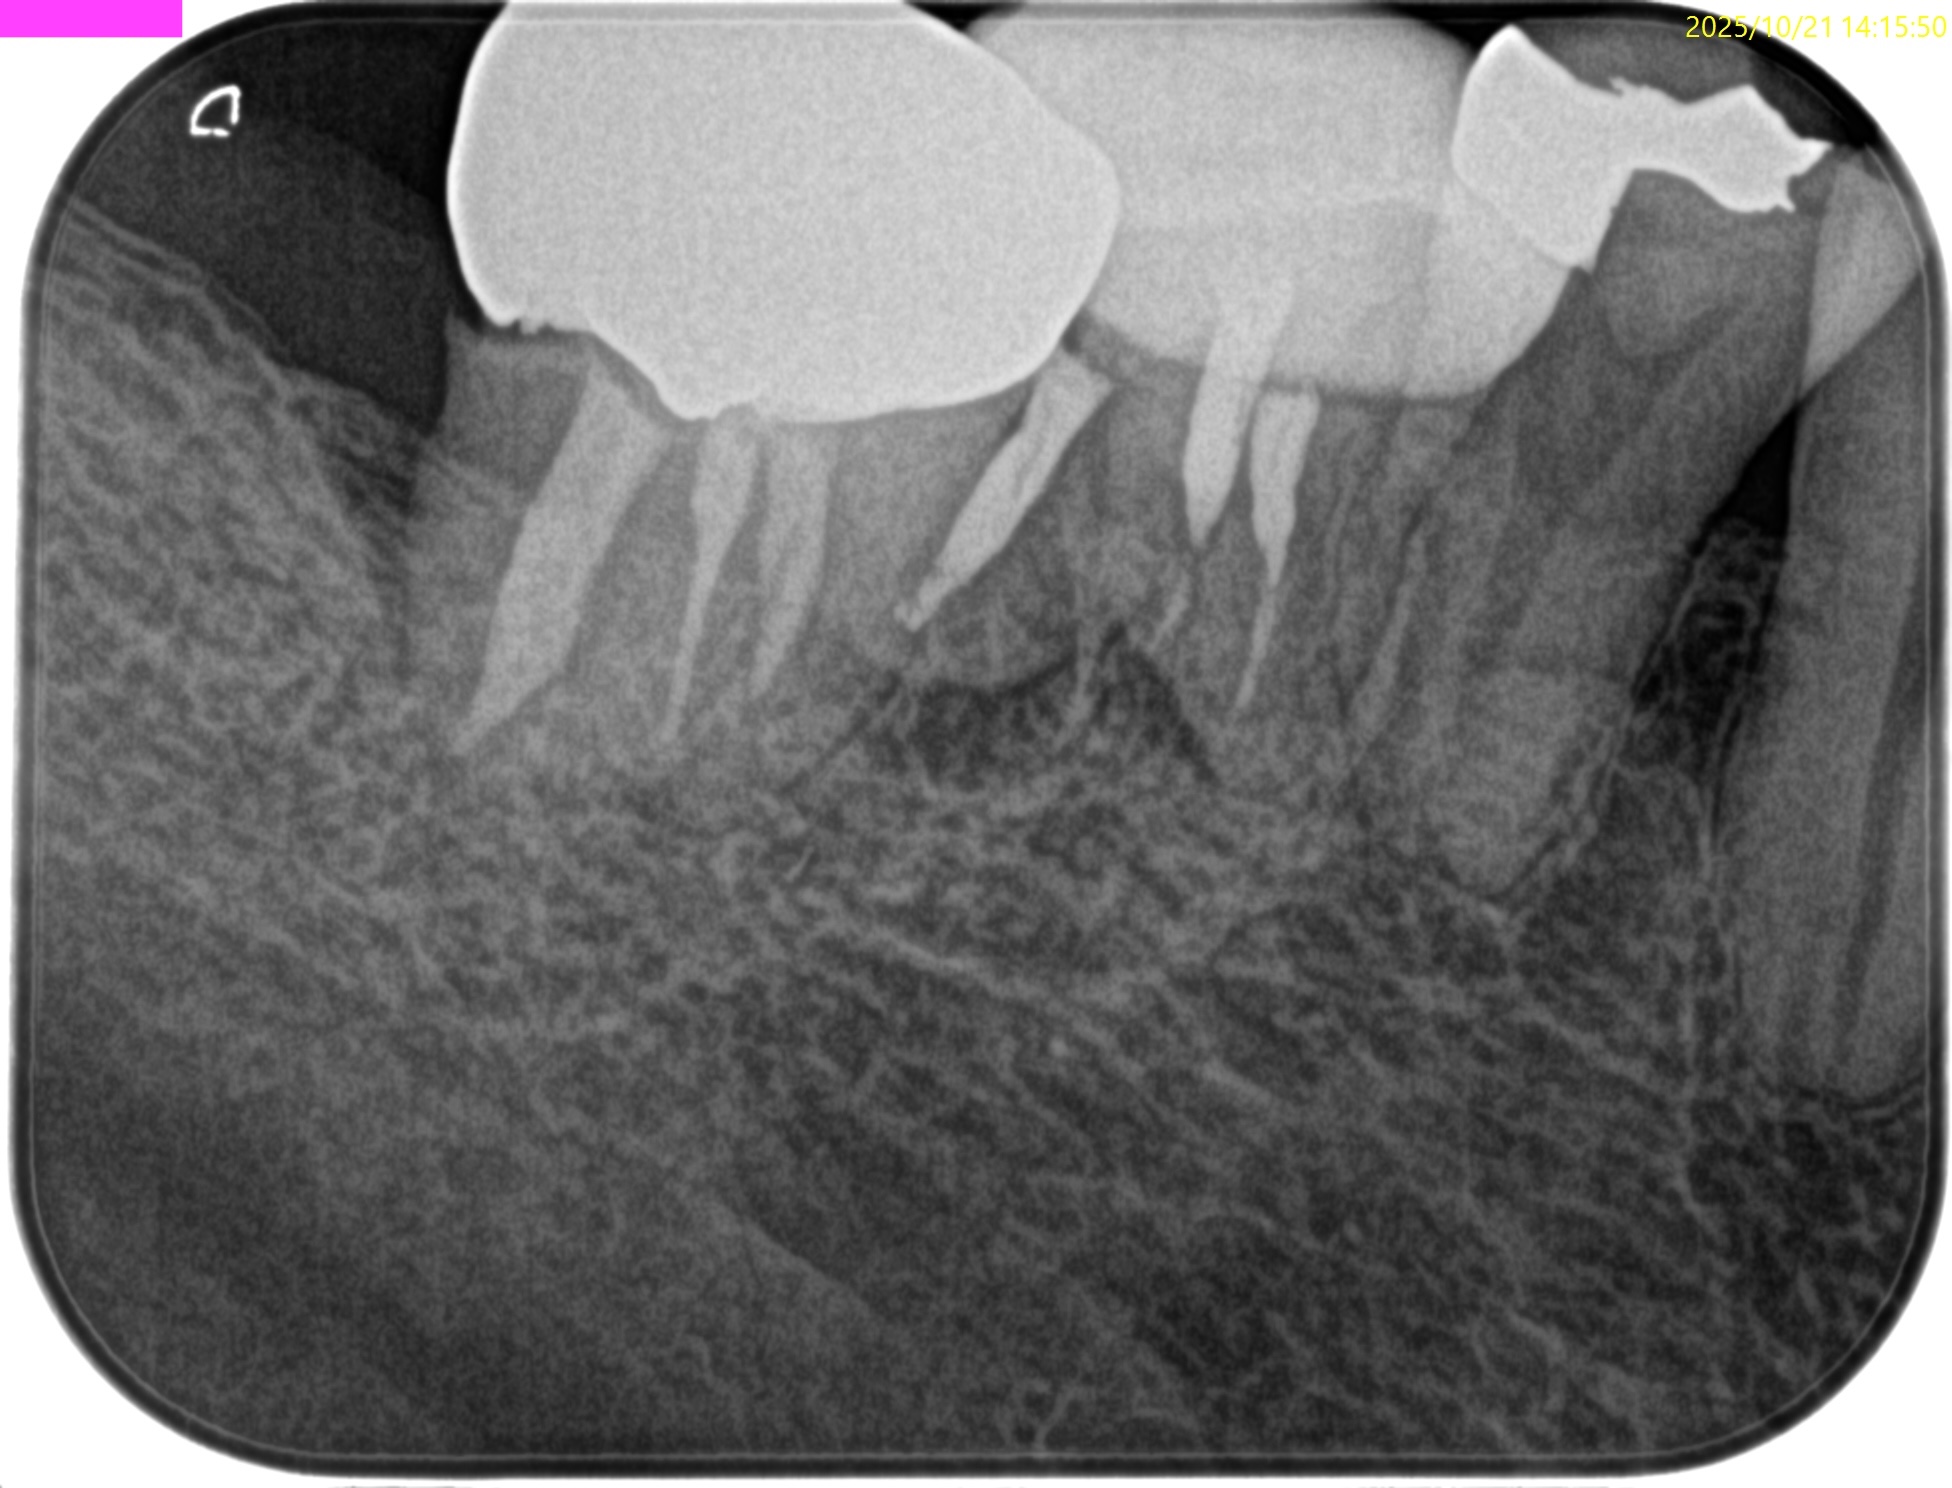

#30 Re-RCT(2025.10.21)

術後にPA, CBCTを撮影した。

#30

MB

ML

D

かかりつけ医にはプロビジョナルレストレーションの装着を依頼した。

次回は半年後である。